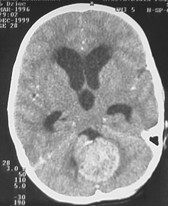

Poniższa rycina obrazuje wynik badania CT po podaniu środka kontrastowego. Badanie wykonano u 7 letniego chłopca z 2 tygodniowym wywiadem ostro narastających bółow głowy z porannymi wymiotami. Klinicznie pacjent prezentował zaburzenia chodu i równowagi, a w badaniu dna oka obraz tarczy zastoinowej. Biorąc pod uwagę przedstawione dane określ, które z poniższych twierdzeń nie są prawdziwe?

1) badanie CT wskazuje na guz okolicy szyszynki;

2) obraz CT przemawia za ostrym obturacyjnym wodogłowiem spowodowanym przez zablokowanie odpływu płynu mózgowo - rdzeniowego w obrębie IV komory;

3) obraz przemawia za rozpoznaniem wstępnym gwiaździaka młodzieńczego robaka móżdżku;

4) postępowaniem z wyboru jest implantacja układu zastawkowego i rozpoczęcie chemioterapii;

5) lokalizacja nowotworu, obraz CT oraz wywiad kliniczny przemawia za szybko rosnącym guzem robaka móżdżku wymagającym pilnego usunięcia.